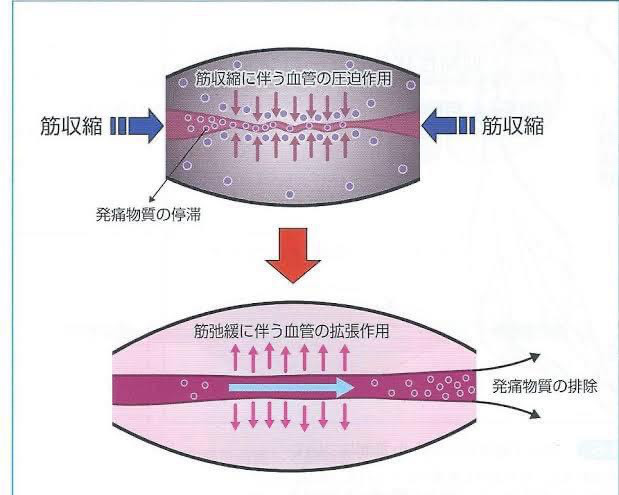

マッサージ屋さんに行ってなんとなく良くなるけど大して変わらないのには筋肉の血流が改善されていない。もしくは全く違う原因なのかもしれません。

筋肉による痛みとは 筋肉には血流が悪くなると(発痛物質)痛み成分が溜まります。 発痛物質が溜まった状態で指圧をすると痛みが出ます。指圧をすることで筋肉の状態が確認できます。

ここで痛みがないのにマッサージを繰り返しても効果は期待できません。 これが一般的な肩こりなどからくる痛みのしくみです。

マッサージは筋肉の血流を良くする手段でありますが、必ずしもマッサージじゃないといけないわけではありません。 自分で痛い筋肉を動かす運動やお風呂で血流をよくするでも良いですし、温めるなど方法はいくらでもあります。